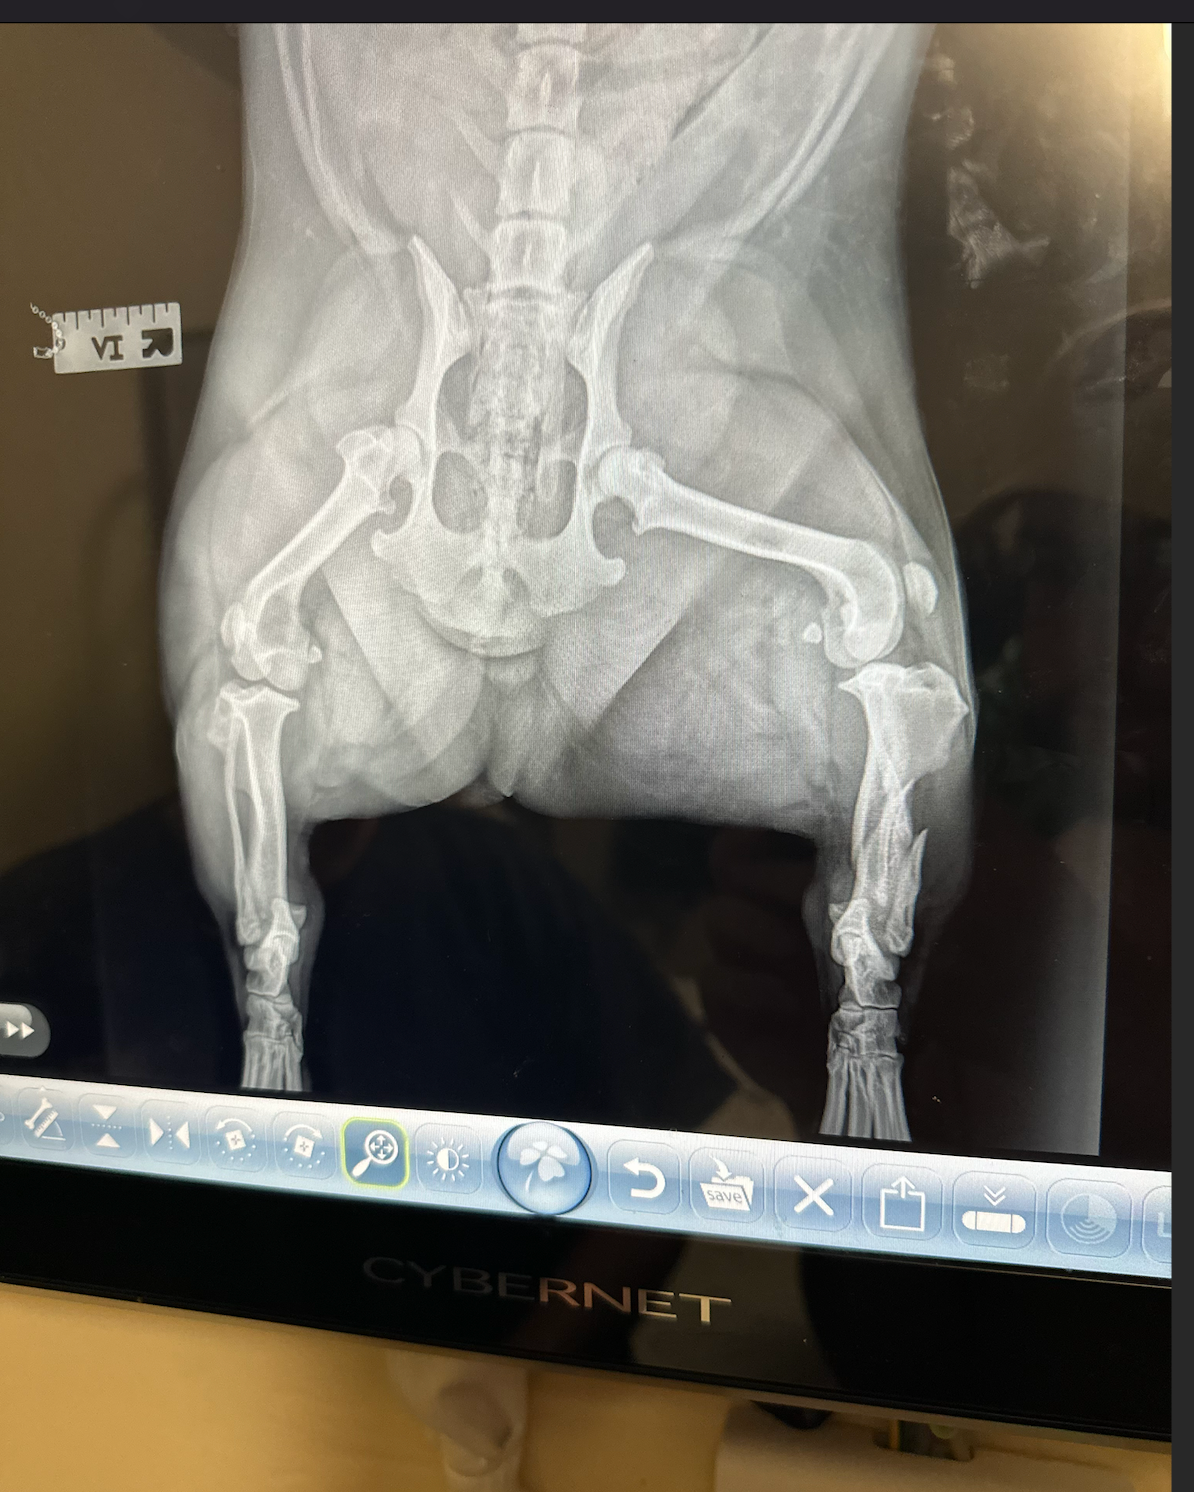

His tibia is fractured, and they are unsure about his fibula due to the X-ray positioning.